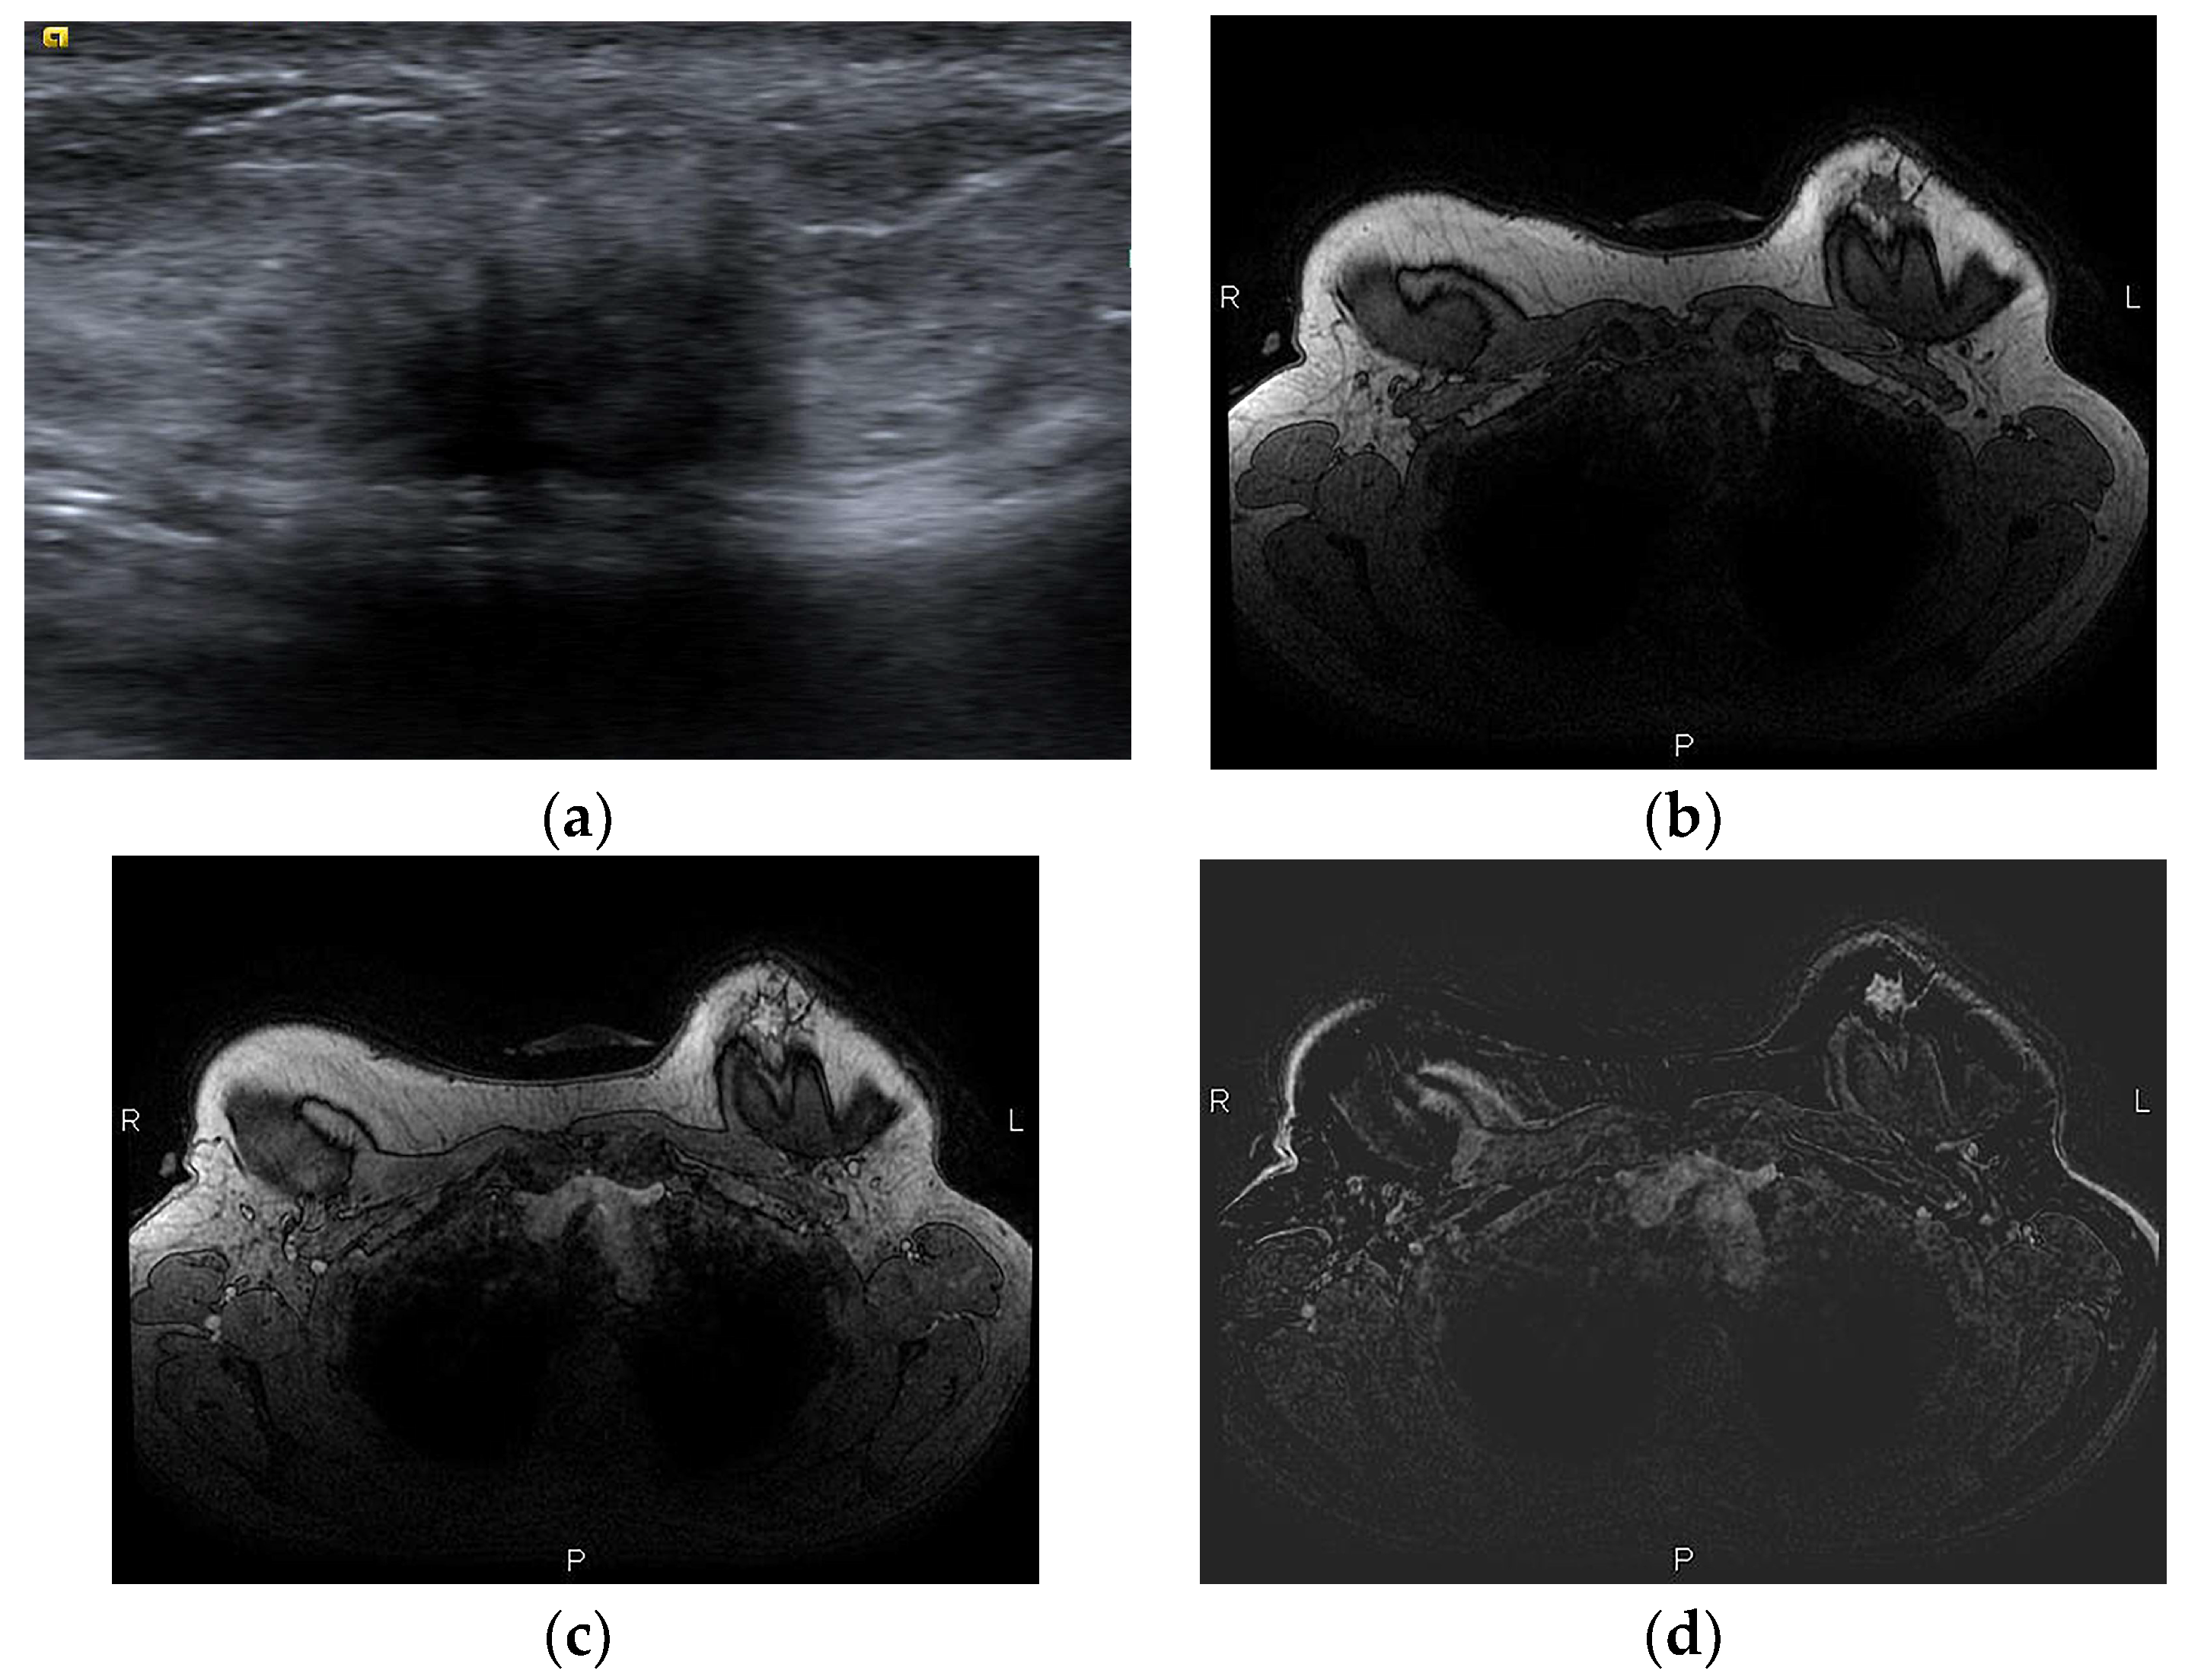

- Sharma, B.; Jurgensen-Rauch, A.; Pace, E.; Attygalle, A.D.; Sharma, R.; Bommier, C.; Wotherspoon, A.C.; Sharma, S.; Iyengar, S.; El-Sharkawi, D. Breast Implant-associated Anaplastic Large Cell Lymphoma: Review and Multiparametric Imaging Paradigms. Radiographics 2020, 40, 609–628. [Google Scholar] [CrossRef] [PubMed]

- Adrada, B.E.; Miranda, R.N.; Rauch, G.M.; Arribas, E.; Kanagal-Shamanna, R.; Clemens, M.W.; Fanale, M.; Haideri, N.; Mustafa, E.; Larrinaga, J.; et al. Breast implant-associated anaplastic large cell lymphoma: Sensitivity, specificity, and findings of imaging studies in 44 patients. Breast Cancer Res. Treat. 2014, 147, 1–14. [Google Scholar] [CrossRef] [PubMed]

- Rotili, A.; Ferrari, F.; Nicosia, L.; Pesapane, F.; Tabanelli, V.; Fiori, S.; Vanazzi, A.; Meneghetti, L.; Abbate, F.; Latronico, A.; et al. MRI features of breast implant-associated anaplastic large cell lymphoma. Br. J. Radiol. 2021, 94, 20210093. [Google Scholar] [CrossRef]

| Delayed, persistent (±mass) | BIA-ALCL, BIA-SCC | ||